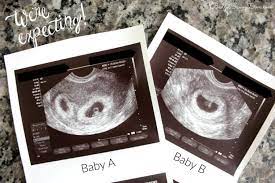

The exact time twins can be detected depends on the type of twins, for example, if they're identical (from one egg) or not. By eight weeks of your twin pregnancy, your babies will have buds for limbs that look like little paddles. Mehr als 200.000 maschinen sofort verfügbar. Most doctors will schedule an ultrasound somewhere between 6 and 10 weeks of pregnancy to confirm the pregnancy and check for multiples. Six full weeks is when you're 6+0 weeks pregnant. I should be 7 weeks, 4 days according to last period. (florida) i suspected i had twins because my beta numbers were high, i had two big follicles during my iui and i'm already big for less than 7 weeks! Seeing twins at 6 weeks is definitely possible. Besides ultrasound at 4 weeks, there are several changes during pregnancy for moms to expect. By four weeks, twins will start showing during ultrasound in form of 2 gestational sacs, but you cannot get clear indication of twins until 6 weeks. The first time i spotted but the other two were gushes. This was taken at 4 weeks 6 days. Some women would rather not know until both twins are relatively safe, while others want to know even if the chances of losing one twin are high.

We had the wonderful opportunity to see our baby's heart flickering on the screen!!! They said the doctor will call me and they may book an ultrasound in another two weeks. By four weeks, twins will start showing during ultrasound in form of 2 gestational sacs, but you cannot get clear indication of twins until 6 weeks. The ultrasound image is of twins at 4 weeks. No fetal heartbeat detectable at 5 weeks 6 days ultrasound.

Around six weeks, each baby's spinal cord and brain start to develop from their own neural tube. (florida) i suspected i had twins because my beta numbers were high, i had two big follicles during my iui and i'm already big for less than 7 weeks! This pole structure actually has some curve to it with the embryo's head at one end and what looks like a tail at the other end. What are the chances of having twins? You have approximately a 3.35 chance of having twins naturally , without the help of any fertility treatments. Besides ultrasound at 4 weeks, there are several changes during pregnancy for moms to expect. When you're 6 weeks pregnant with twins, you are between 5 weeks+0 days and 5 weeks+6 days pregnant. Taken at 4 weeks, the ultrasound image shows a gestational sac.

Your babies will be developing rapidly but a 6 week ultrasound for twins provides you with more details about your multiples.